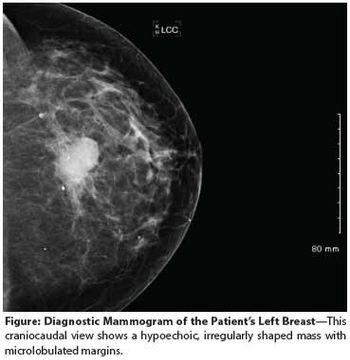

A 24-year-old woman presents to her primary care provider with a mass in her left breast. Examination confirms a 2.2-cm mass in the upper outer quadrant, with a single mobile axillary node that is firm to palpation.